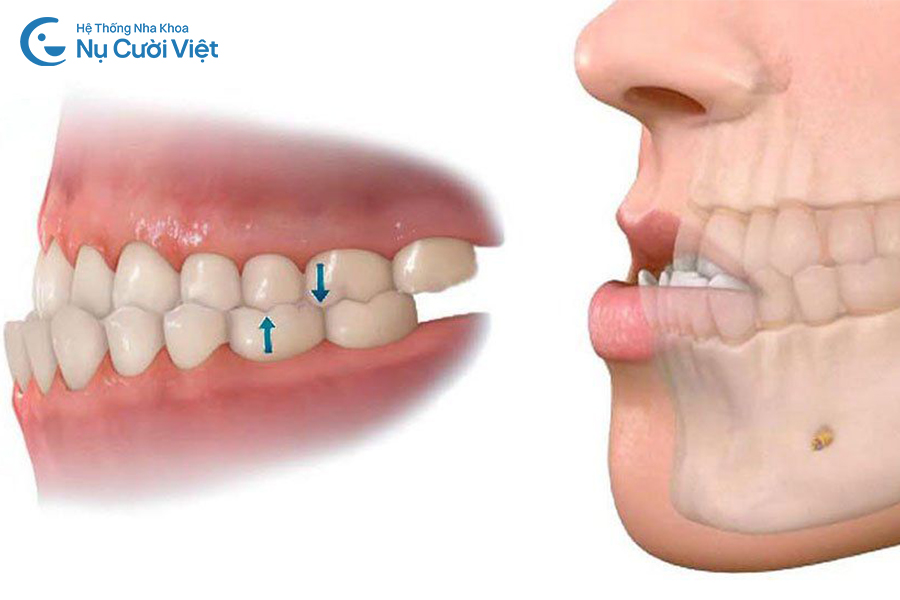

Tỷ lệ mô răng còn lại: Tỷ lệ mô răng thật còn lại ảnh hưởng đến khả năng chịu lực của răng sau khi đã mài để bọc sứ. Khi mô răng còn lại quá ít, răng dễ bị yếu đi, làm tăng nguy cơ nứt, gãy hoặc bong mão trong quá trình chỉnh nha. Bởi các khí cụ chỉnh nha (như dây cung, mắc cài, khay niềng…) sẽ được gắn trực tiếp lên mão răng sứ và tác động lực siết thông qua đó. Vì vậy, đây là yếu tố quan trọng để bác sĩ cân nhắc có nên niềng hay cần thay đổi kế hoạch điều trị.

Răng sau khi được mài để bọc sứ có thể ảnh hưởng đến khả năng chịu lực nếu niềng răng

Răng sau khi được mài để bọc sứ có thể ảnh hưởng đến khả năng chịu lực nếu niềng răng